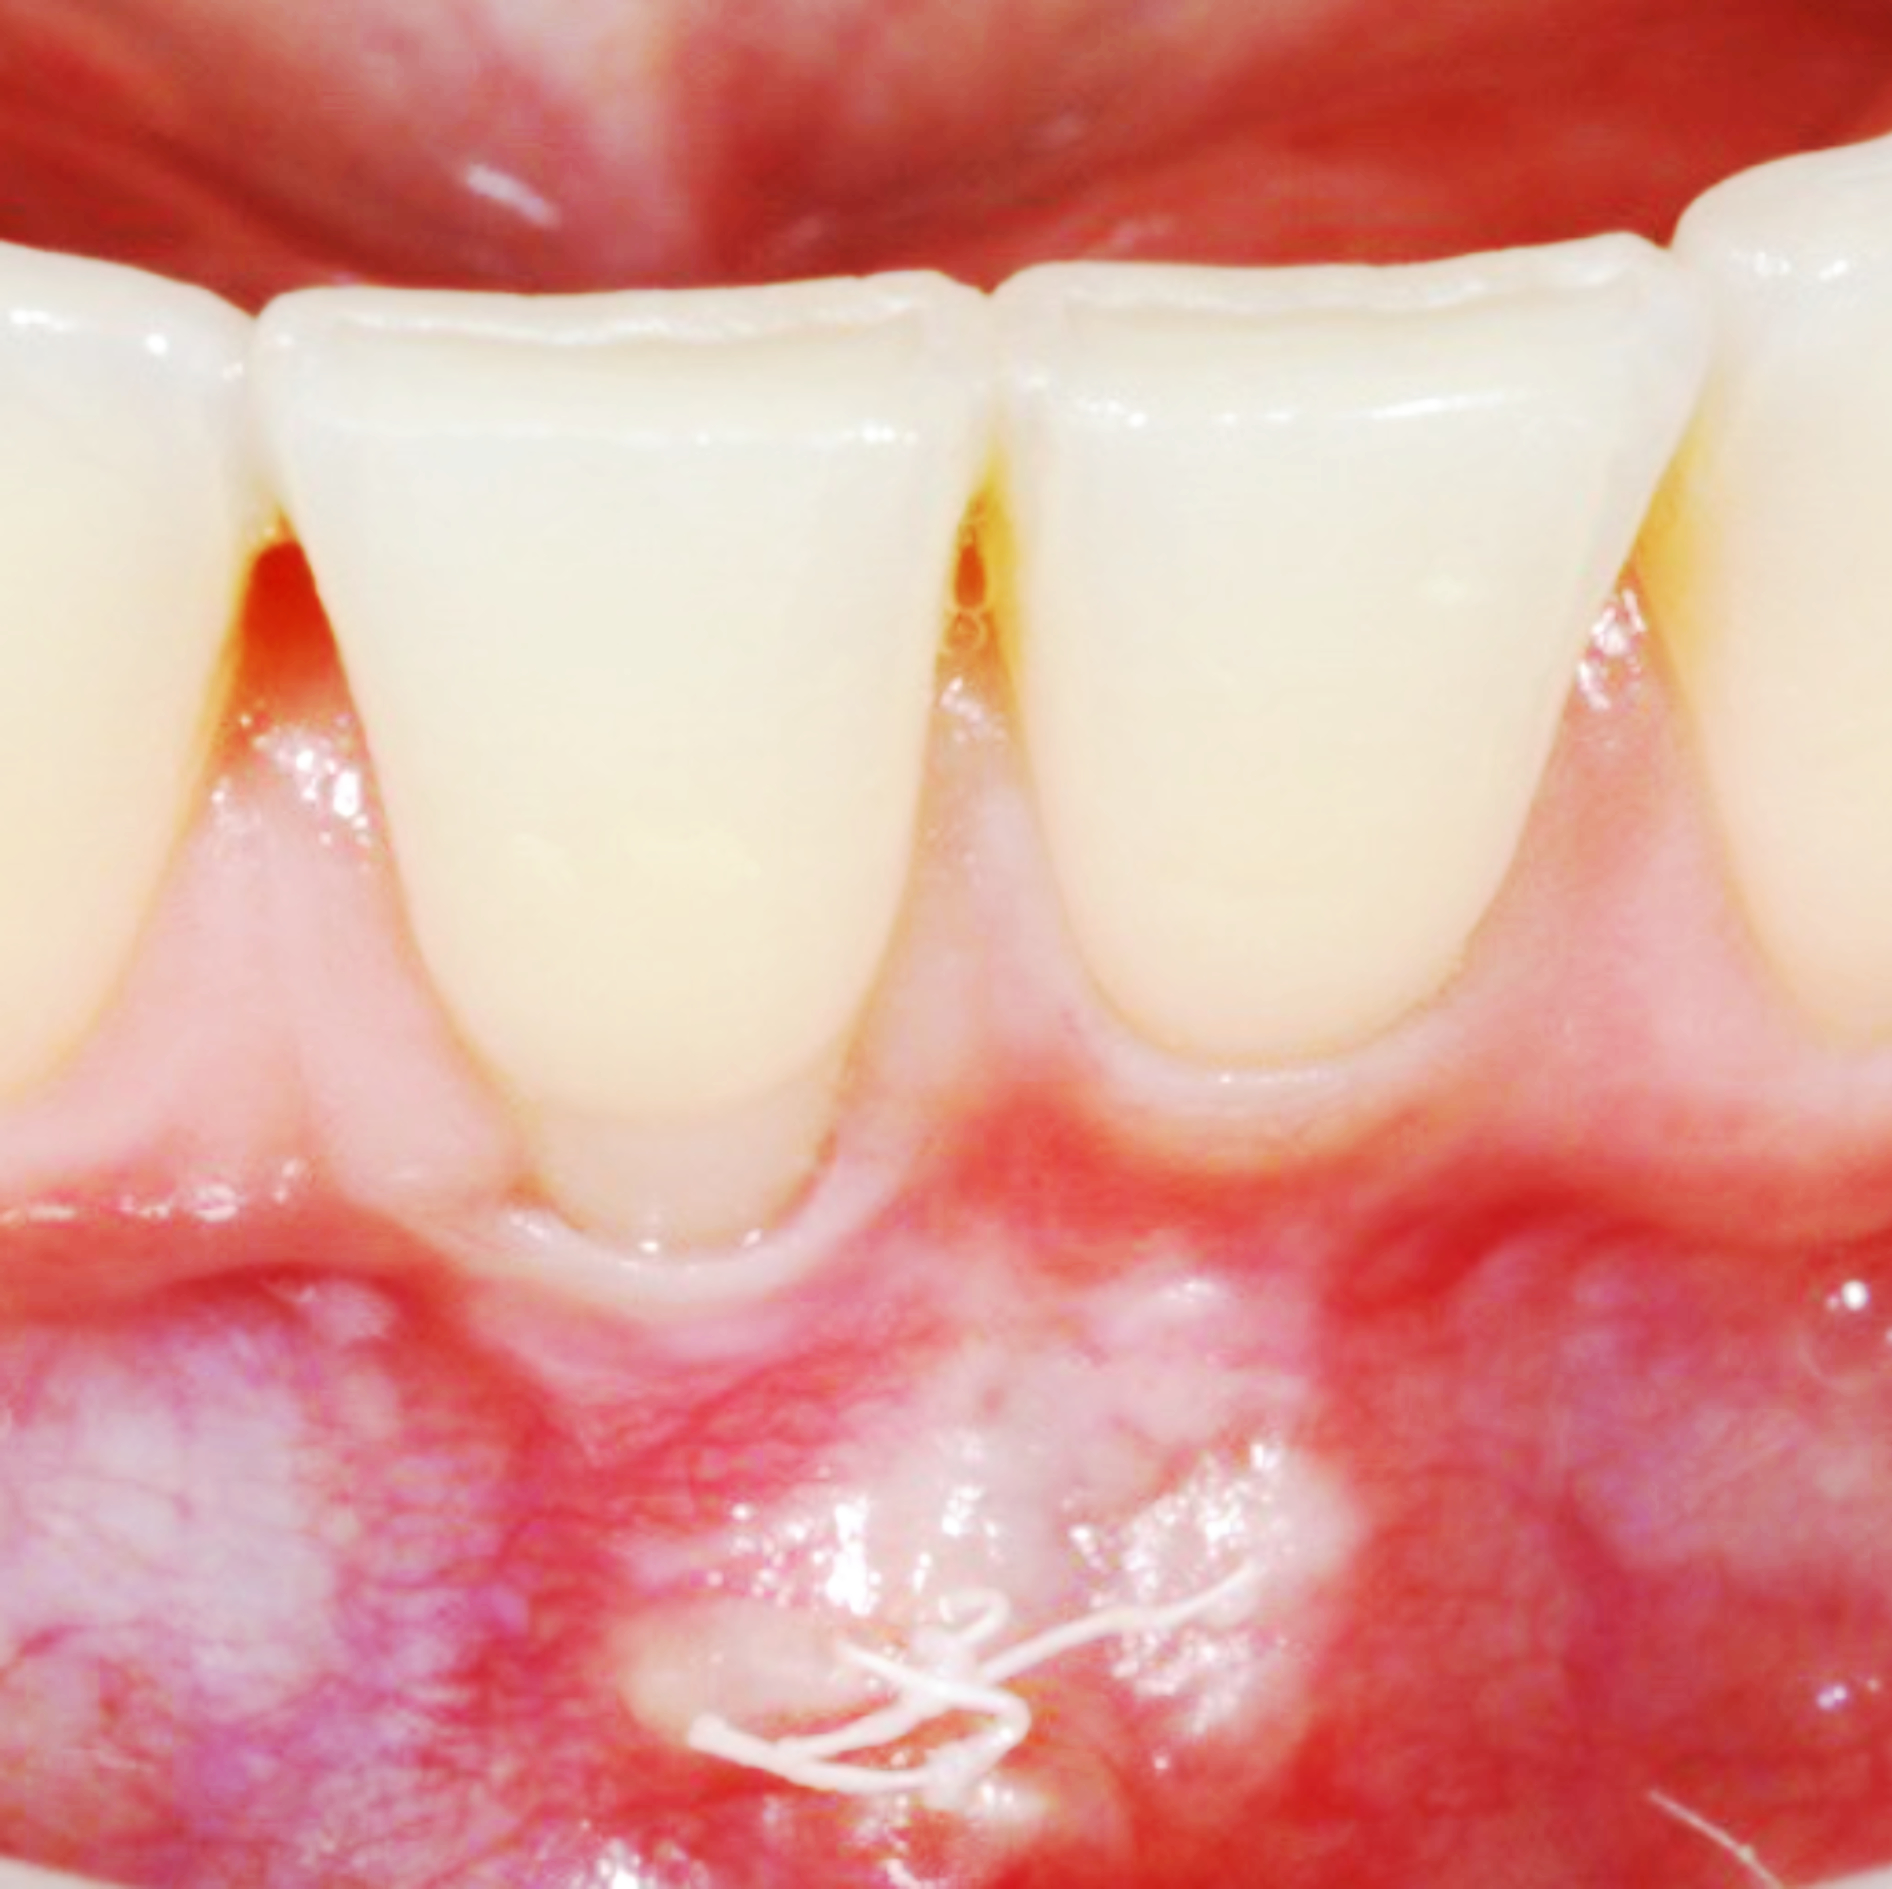

Kasuset er en kvinne på 26 år, frisk uten kjente sykdommer eller allergier. Pasienten bruker minipille. Hun har aldri røykt eller brukt andre nikotinholdige stimulantia. Pasienten fikk utført kjeveortopedisk behandling med fast apparatur i begge kjever i ungdomsårene (2013/2014) der tann 14 og 24 ble ekstrahert på grunn av uttalt horisontalt overbitt. Etter avsluttet kjeveortopedisk behandling ble det i front overkjeve og underkjeve pålimt en palatinal/lingval retensjonstråd. I februar 2022 ble pasienten henvist fra offentlig tannlege til Spesialistutdanningsklinikken, UiB, for vurdering og eventuell behandling av gingival retraksjon labialt 41. Ifølge henvisningen har pasienten den siste tiden merket en rask utvikling av en labial retraksjon 41 som opplevdes betent og øm. Ved henvisningstidspunktet ble retraksjonen målt til 5 mm i vertikal, 4 mm i horisontal retning og med en labial sulkusdybde på 2 mm (figur 1A). Den gingivale fenotype ble generelt vurdert som tynn, men vurderingen labialt 41 var vanskelig på grunn av manglende keratinisering og ett aktivt lokalt fiberdrag mot margo gingiva. Ved aktivt strekk fra frenulum ble den marginale delen av gingiva dradd bort fra tannoverflaten som kan gi økt plakkakkumulering i sulkusområdet (figur 1A). Vevstykkelsen labialt 41 ble ikke vurdert med periodontal sonde i sulkus. Akseretningen på 41 ble karakterisert som nøytral. Basert på kliniske og røntgenologiske funn ble retraksjonen klassifisert som Miller klasse II: Retraksjon til eller apikalt for den mukogingivale grense uten periodontalt festetap approksimalt [8]. Etter Cairos klassifisering ble defekten klassifisert som en RT 1: Labial retraksjon uten festetap approksimalt (figur 1A og 1B; [9]).

Figur 1, A-B. Gingival retraksjon labialt på tann 41 med lokalt fiberdrag mot margo gingiva uten keratinisert, festet gingiva koronalt for fiberfestet (A). Bildet er tatt ved henvisningstidspunktet. Røntgenbilde av tann 41 uten påvisbart approksimalt festetap (B).